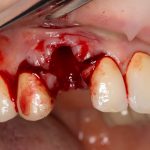

Рекомендации по установке имплантов. Для всех. Часть V.